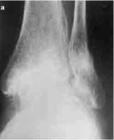

3、X線攝片,在出現症狀的1—2周內常無明顯異常,3—4周后可見一橫形骨折線,周圍有骨痂形成,病程長者,骨折周圍骨痂有增多趨向,但骨折線更為清晰,且骨折端有增白,硬化徵象,因此,當臨床疑有疲勞骨折,而X線檢查又是陰性時其早期診斷方法是進行放射性核素骨顯象。